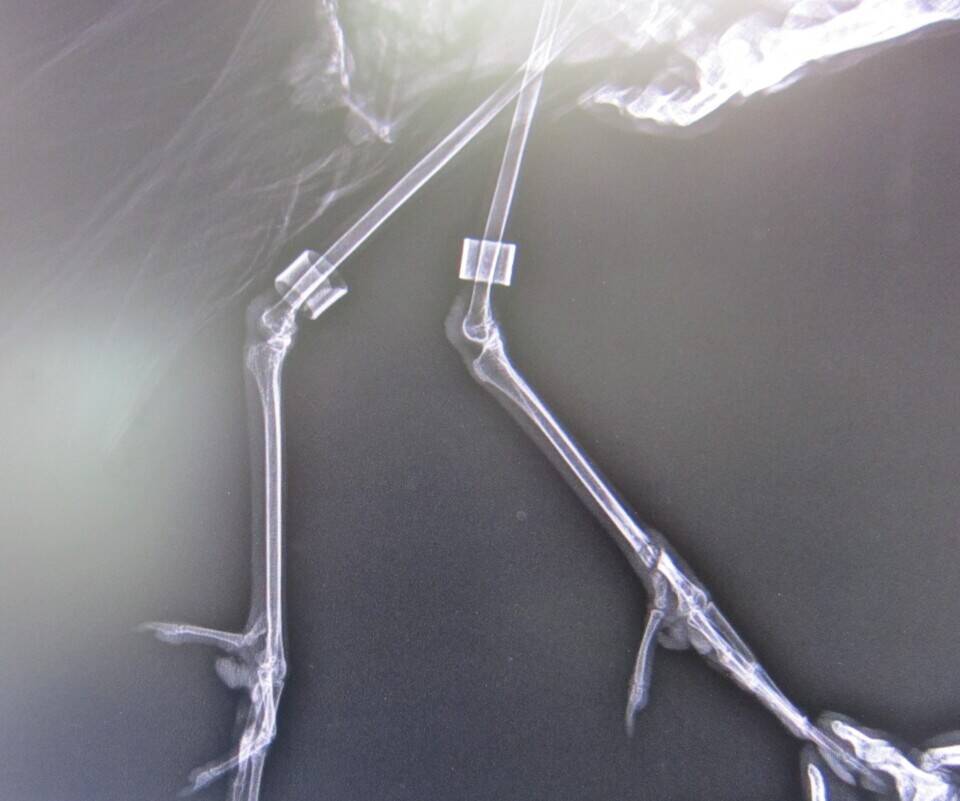

バードケージつながりでもう1枚。

これはブロンズトキの脚の写真です。

向かって右側が左脚で、ケガしたのもこの脚です。

さてどこが悪いのでしょうか?

左右の脚を見比べてみればすぐにわかるはず。

正解は・・・

はい、ここ、このふしょ骨という骨が折れていました。

重傷なので入院させ、しばらく副子(添え木のこと)をあててテーピングしていたところ、無事完治!

すでにバードケージに戻って、以前通りの生活を送っています。